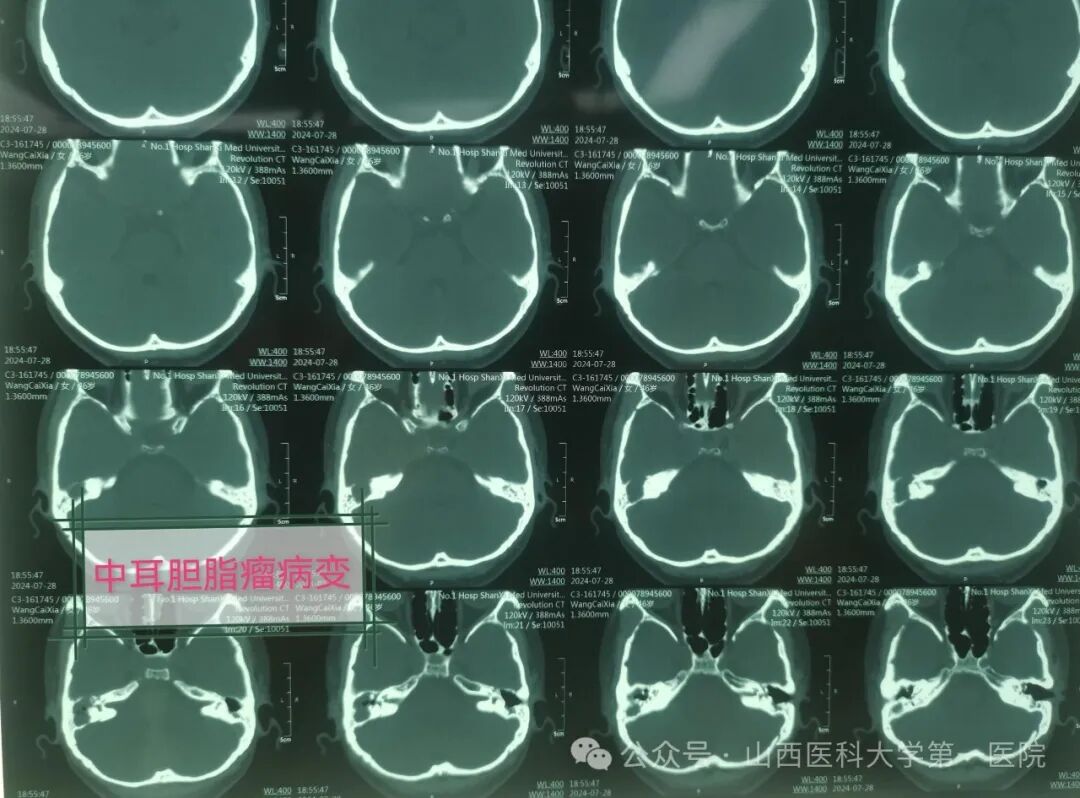

今年46岁的张女士,既往有中耳炎病史,最近半年多以来发现单侧耳总是流水,感冒发炎后加重,伴有听力减退,有时出现偏头痛,对症药物治疗效果不佳,最近1月余,症状逐步加重,同时出现头闷与头昏,甚至有走路失衡情况,并出现进行性面瘫现象,就诊于山西医科大学第一医院耳鼻咽喉-头颈外科,做影像学相关检查后被医生确诊为中耳胆脂瘤、面神经麻痹、迷路炎与迷路瘘管、局限性脑膜炎。

主刀医生张海利教授介绍,慢性化脓性中耳炎属于耳科常见疾病,而中耳炎胆脂瘤属于其中较为危险的一种类型。胆脂瘤并非平时所说肿瘤,是位于中耳与乳突腔内囊性结构,有脱落上皮细胞堆集、中央坏死,像滚雪球一样,越聚越大而形成。胆脂瘤患者临床上可出现耳流脓、耳痛、耳闷塞感及听力下降等症状,耳流脓一般呈持续性或间断性,有特殊恶臭味,有时伴有血性分泌物。胆脂瘤具有潜在危害,逐渐增大时会压迫并侵蚀周围骨质,并向邻近组织扩散,严重者可出现脑膜炎、眩晕以及面瘫等颅内外并发症。此例中年女性患者胆脂瘤破坏范围较大,中颅窝脑板已经破坏,形成局限性脑膜炎并发症,而且现在已有偏头痛的症状,同时在手术中发现内耳水平半规管与后半规管破坏,形成迷路瘘管与迷路炎,面神经骨管裸露破坏,医生在显微镜下仔细清理病变组织包括胆脂瘤与肉芽组织,经过乳突根治、面神经减压以及内耳迷路修补治疗,手术获得圆满成功。术后,张女士病情得到基本控制,经过消炎消肿抗感染以及对症治疗后即可出院。